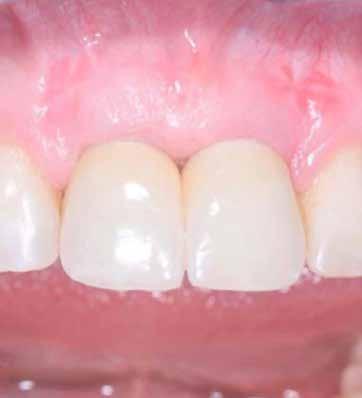

A sebészeti eljárás

Mind a hat implantátum esetén kétlépcsős műtétet végeztünk. Minden sebészeti eljárást bódítás, illetve preoperatív szisztémás antibiotikus terápia nélkül végeztünk. A négy eset közül kettőnél leukocitában és vérlemezkében gazdag fibrint (L-PRF) alkalmaztunk a beavatkozás során (IntraSpin, BioHorizons; 2. táblázat). Minden esetben a pontos CERALOG menetvágási (maximum 15 ford./perc) és fúrási (maximális fúrási fordulatszám: 550–800 ford./perc) protokollt követtük. Az összes implantátumot manuálisan helyeztük be 35 Ncm maximális nyomatékkal. Az implantátumokba PEEK zárócsavar került (2. ábra). A lágyszövetet atraumatikus, felszívódó varrattal, szorosan zártuk/összevarrtuk. A műtétek után szövődmények nem jelentkeztek. A pácienseket arra kértük, hogy a műtét utáni héten naponta kétszer öblögessenek klórhexidinnel (PERIO-AID, 0,05%, DENTAID). Az alsó állcsontnál három hónapos, a felső állcsontnál öt hónapos gyógyulási időt vettünk figyelembe. Három hónap (1. eset) és öt hónap (2., 3. és 4. eset) elteltével a műtétek második stádiumát helyi érzéstelenítés mellett végeztük. A gyógyu-

lási csavarokat (PEEK titáncsavarral) maximum 15 Ncm-rel húztuk meg (3–6. ábra). Az összes implantátum kiváló stabilitást mutatott (a mérésekhez Periotestet használtunk, a Medizintechnik Gulden jóvoltából), és teljesen osszeointegrálódott. Ezt a radiológiai vizsgálatok is megerősítették.